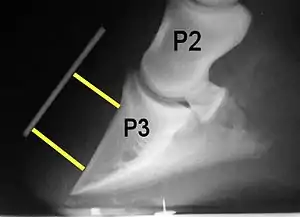

Rotation is the most common form of displacement, and, in this case, the tip of the coffin bone rotates downward.[4] The degree of rotation may be influenced by the severity of the initial attack and the time of initiation and aggressiveness of treatment. A combination of forces (e.g. the tension of the deep digital flexor tendon and the weight of the horse) result in the deep digital flexor tendon literally pulling the dorsal face of the coffin bone away from the inside of the hoof wall, which allows the coffin bone to rotate. Also, ligaments attaching the collateral cartilages to the digit, primarily in the palmar portion of the foot, possibly contribute to a difference in support from front to back. The body weight of the animal probably contributes to rotation of the coffin bone. Rotation results in an obvious misalignment between PII (the short pastern bone) and PIII (the coffin bone). If rotation of the third phalanx continues, its tip can eventually penetrate the sole of the foot.

Several radiographic measurements, made on the lateral view, allow for objective evaluation of the episode.

- Palmar angle (PA): the angle between a line perpendicular to the ground, and a line at the angle of the palmar surface of P3.